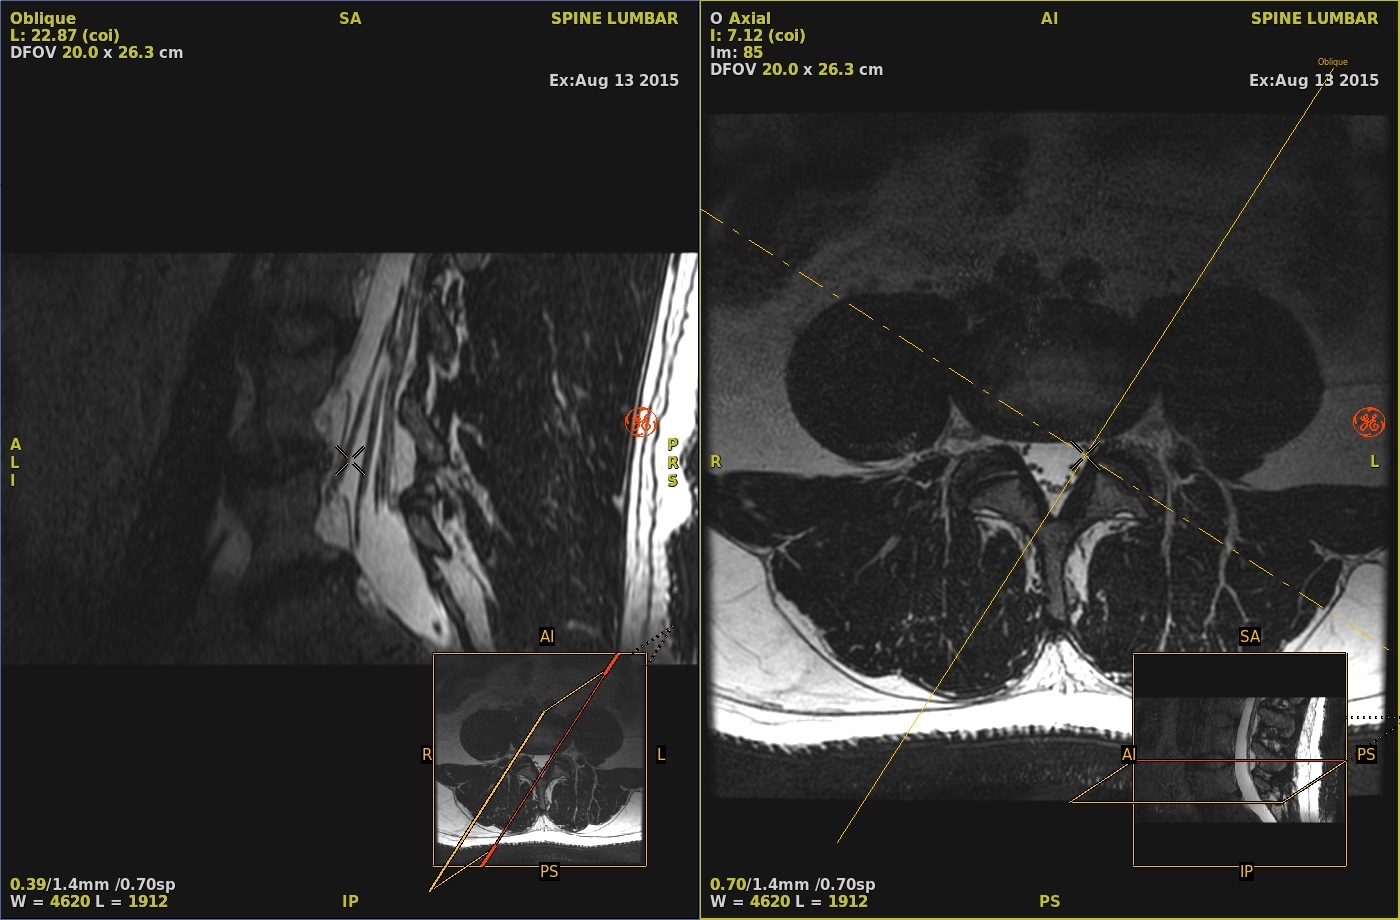

A solid yellow line appears which represents the plane of the Oblique reformat.

Figure 1. Single-oblique lines

- Place the cursor on the solid yellow line and click and drag to tilt the yellow line to display the desired plane.